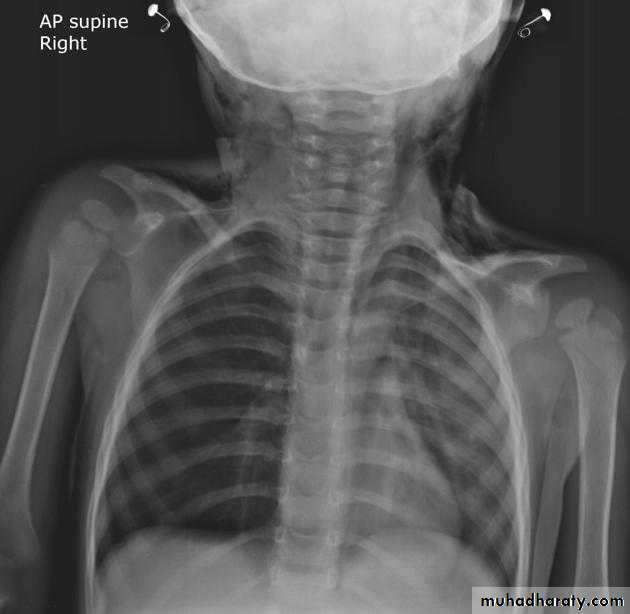

Chest radiographs are the most commonly used examination to assess for presence of a pleural effusion, however it should be noted that on a routine erect chest x-ray as much as 250-600 ml of fluid is required before it becomes evident 6. A lateral decubitus film is most sensitive, able to identify even a small amount of fluid. At the other extreme, supine films can mask large quantities of fluid.

CXR (lateral decubitus)

A lateral decubitus film (obtained with the patient lying on their side, effusion side down, with a cross table shoot through technique) can visualise small amounts of fluid layering against the dependent parietal pleura.